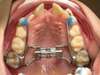

Après disjonction

Après traitement